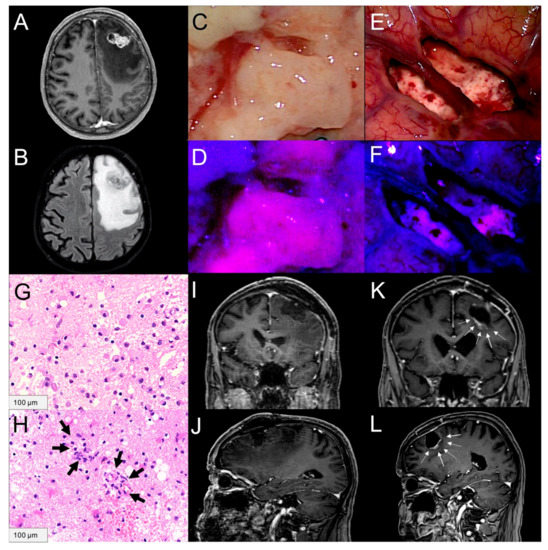

2.3. 5-ALA Fluorescence Characteristics of Peritumoral Brain Tissue

2.4. Tissue Samples from Peritumoral Brain Tissue and Histopathology

2.4.1. Tumor Cell Infiltration

2.4.2. Angiogenesis

4.3. Histopathological Assessment